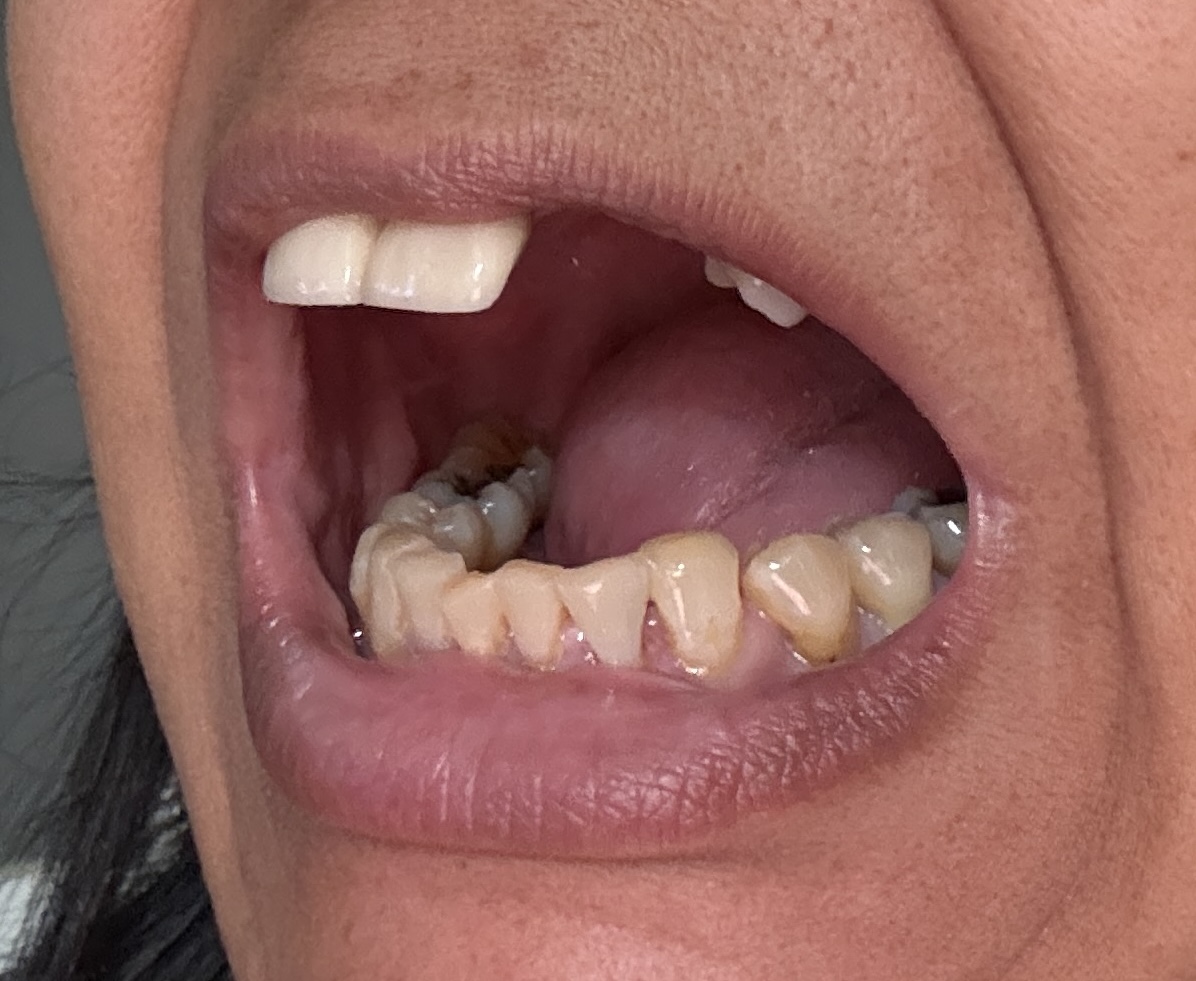

Dental Auction No. 11561: Several extractions and All-on-4 Top and bottom arches

12,13,14 have had root canals in past and now have quite a bit movement. 2-5 have all had root canals in past and now the crowns are breaking down.

Overall information (lower arch)

Overall, all of my gums have receded and most of the bottom teeth are exposed w/ some roots and there are many cavities.